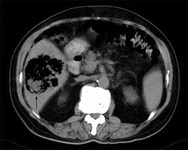

Aneurisma da aorta abdominal: tomografia computadorizada (TC) de um aneurisma da aorta abdominal roto

University of Michigan, mais especificamente os casos do Dr. Upchurch, representando os Departamentos de Cirurgia vascular e Radiologia